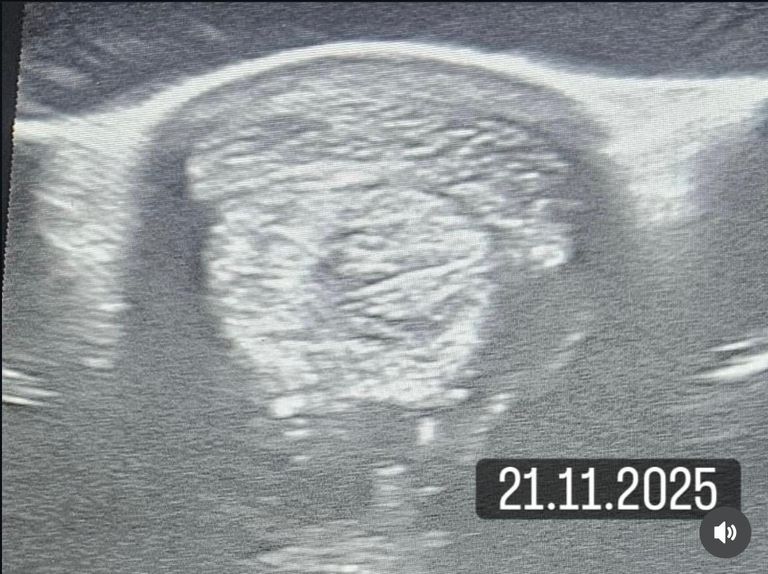

Nach 10 Behandlungen und konsequenter Betreuung kam gestern, am 21.11., der Kontrolltermin beim Tierarzt

und die unglaubliche Nachricht: Der Sehnenschaden ist vollständig ausgeheilt!